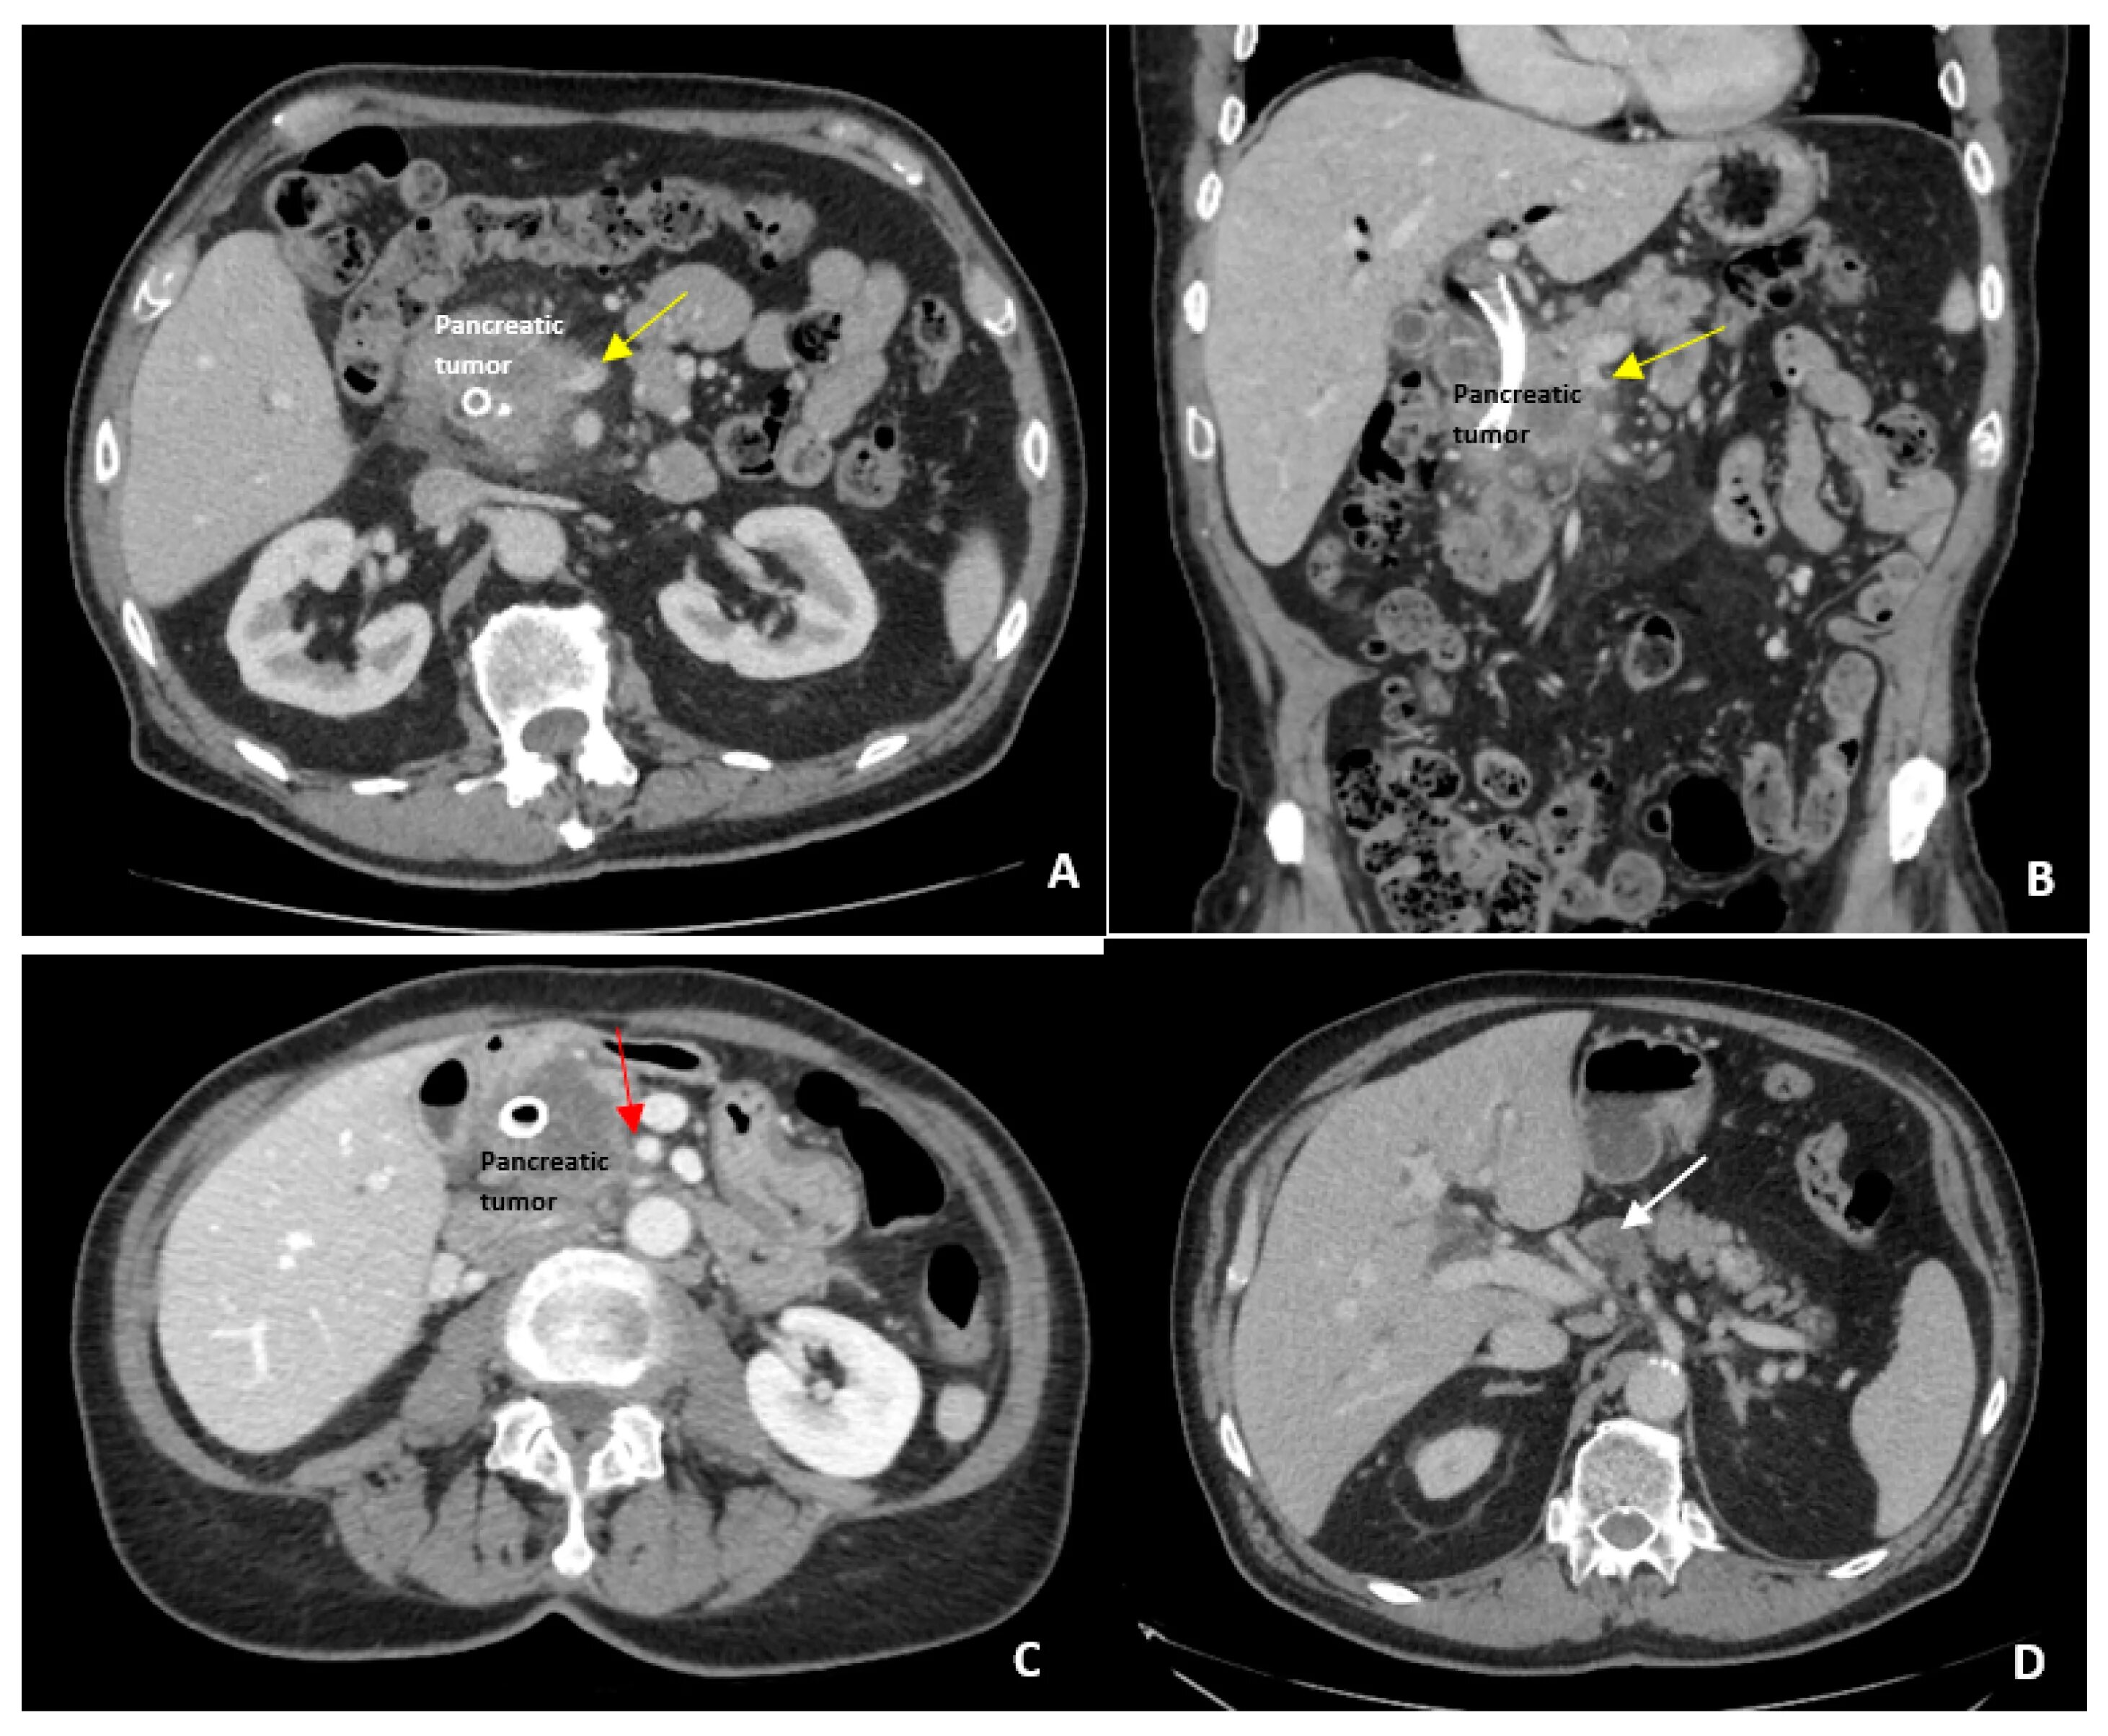

Ct search